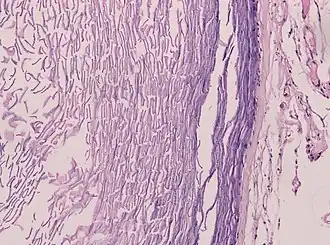

Epidermoid cysts are usually diagnosed when a person notices a bump on their skin and seeks medical attention. The definitive diagnosis is made after excision by a pathologist based on microscopic appearance of a cystic lesion lined by cornified epithelium containing lamellated keratin without calcifications. They can also be seen as isointense lesions on MRI or hyperintensities on FLAIR.

Histopathology showing epithelium and lamellated keratin (left) Histopathology showing epithelium and lamellated keratin (left)